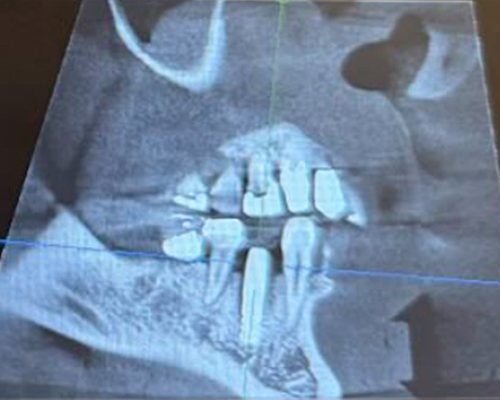

米国の技術×専属技工士×精密機器のフル活用で「短期治療」を実現!

米国の先端治療を安価で

インプラント、マウスピース矯正、小児矯正の歯医者なら「ALBA歯科&矯正歯科」。東京・神奈川・海外を中心に26医院を展開する当グループの専門治療をご案内します。年間1,000症例以上の「世界レベル」オペを実施しているインプラント治療では最安で税込99,800円~の低価格を実現。目立たずメンテナンスも容易と好評の透明なマウスピース矯正は月3,300円からご提供が可能です。重度の歯周病でも徹底的な検査と滅菌で再発を防止し、包括治療で早期解決します。低価格・低リスクの「小児専門」矯正治療を実現、通常100万円ほどかかるワイヤー矯正と比べ、半額程度の費用で矯正治療がおこなえます。年中無休で土・日・祝日も診療中。朝10時台から夜20時(鶴ヶ峰院、上永谷院は19時)まで受診可能。

年間1,000症例以上の 「世界レベル」オペ実施

最安で税込99,800円~の低価格を実現